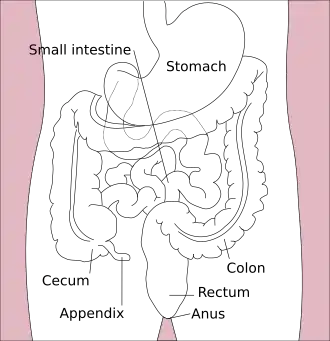

| Ilustração do trato digestivo inferior | |